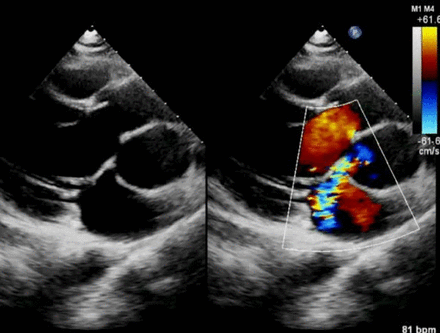

Case 1

Case 2